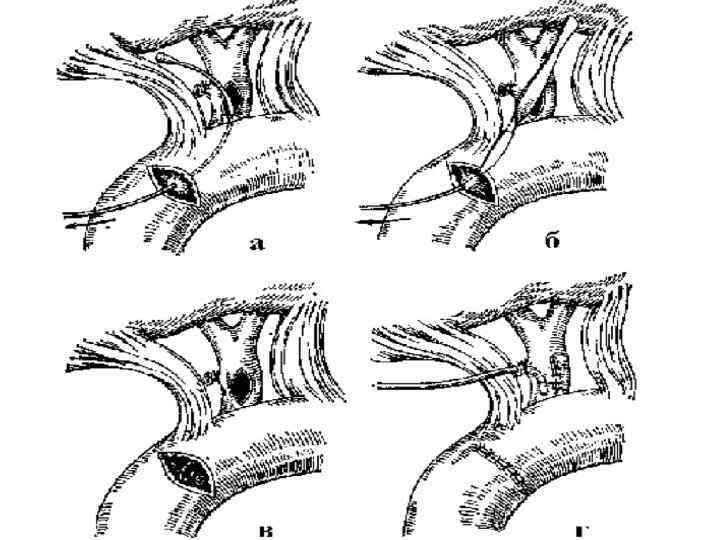

Холедохотомияны аяқтау: 1. тігіп тастау, 2. сыртқы дренаждаумен, 3. трансдуоденальды сфинктеротомия, 4. холедоходуоденоанастомоз Сыртқы дренаждау Т -образным дренажом (по Керу) (А); Т-образным расщепленным дренажом (по Вишневскому) (Б); через культю пузырного протока (по Холстеду) (В).

Трансдуоденальды сфинктеротомия